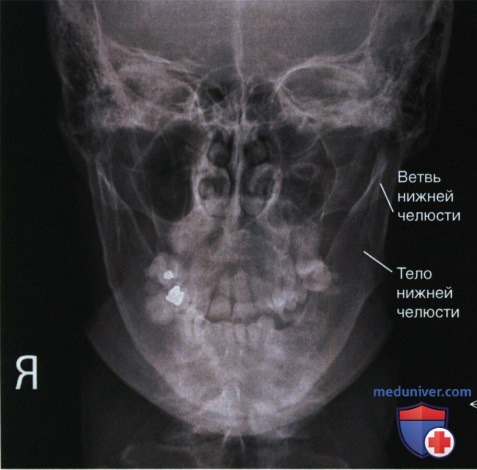

Рентгенография черепа и позвоночника: изображение и диагностика